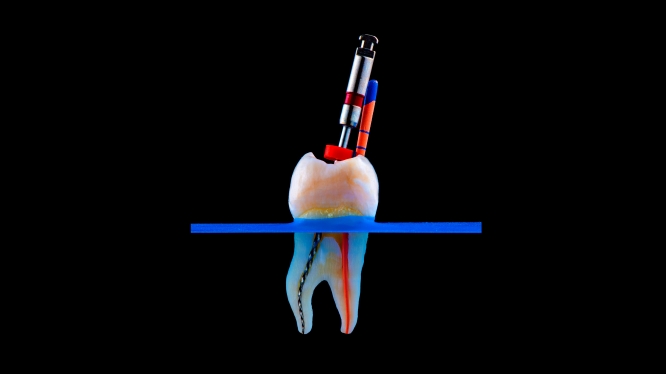

La endodoncia es un tratamiento dental que se realiza cuando el interior del diente está dañado o infectado.

Dentro de cada diente existe una parte llamada pulpa dental, donde se encuentran:

- Nervios

- Vasos sanguíneos

- Tejido vivo

Cuando esta zona se infecta o se daña, es cuando se necesita una endodoncia.

🛠 ¿Qué hace el tratamiento?

- Elimina la infección

- Limpia el interior del diente

- Desinfecta completamente

- Sella el diente para evitar que vuelva a infectarse

🔬 ¿En qué consiste el tratamiento de conducto?

🧩 Paso a paso de una endodoncia

- Diagnóstico 🩺

El dentista evalúa el diente con estudios clínicos y radiografías para confirmar el daño. - Eliminación del nervio dañado ⚡

Se retira la pulpa infectada o dañada del interior del diente. - Limpieza y desinfección 🧼

Se limpian los conductos internos para eliminar bacterias y residuos. - Sellado del conducto 🔒

Se rellenan y sellan los conductos para evitar futuras infecciones.